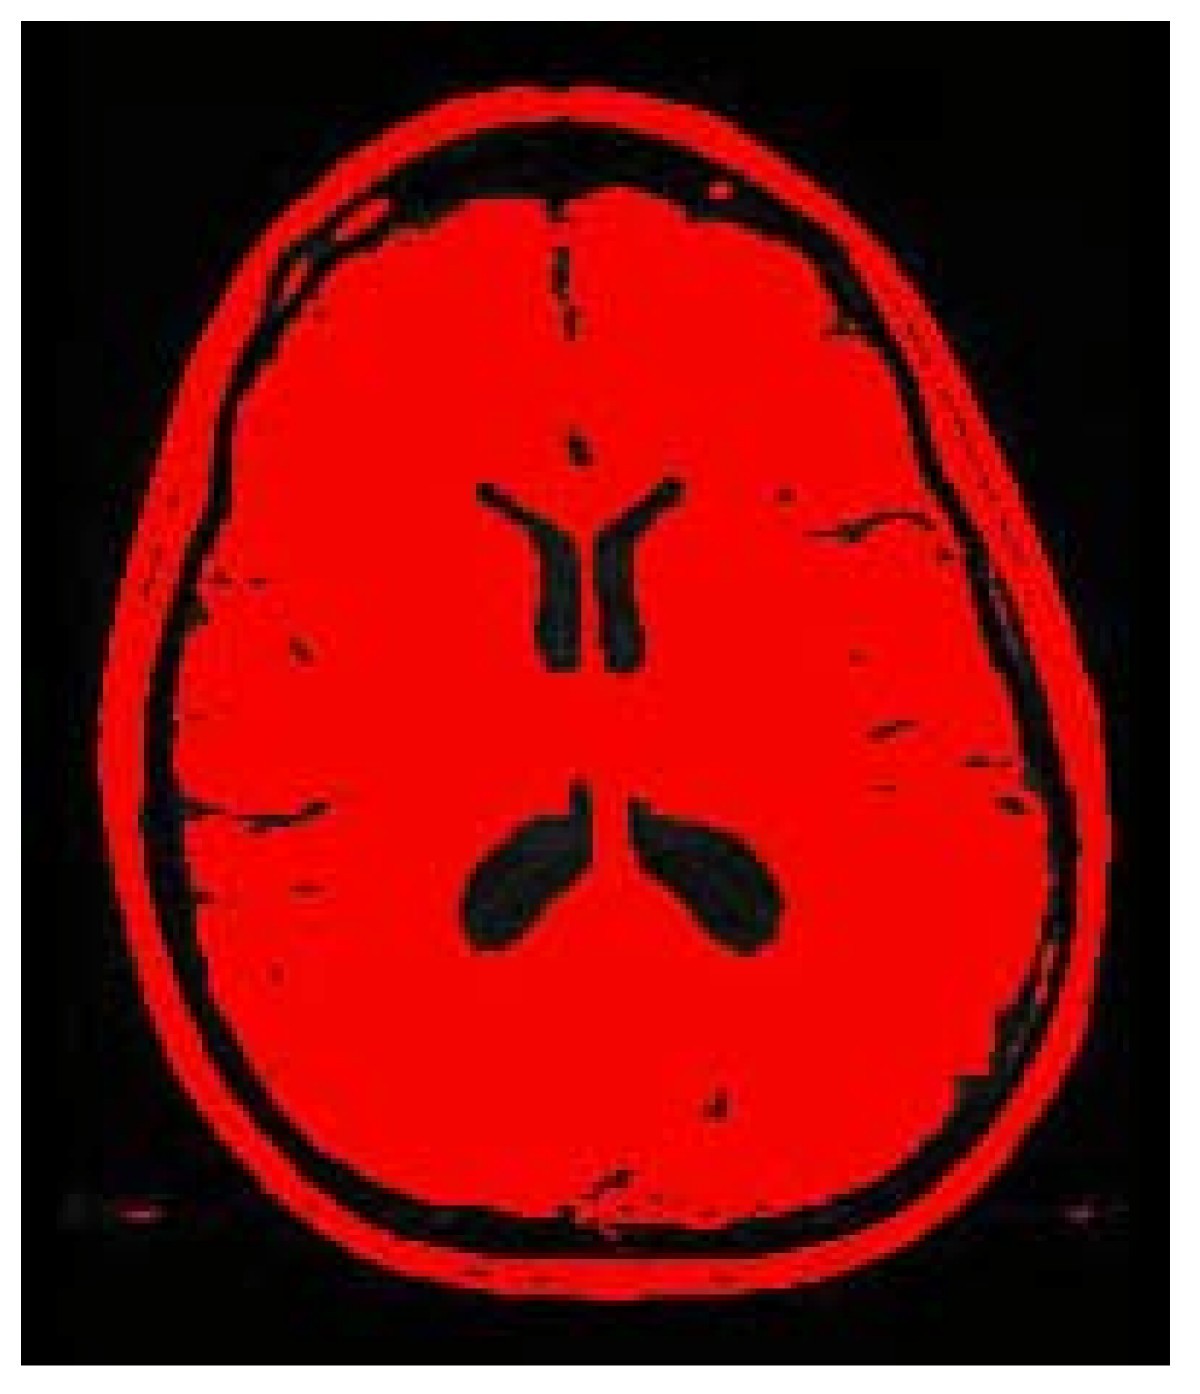

Threshold image

.